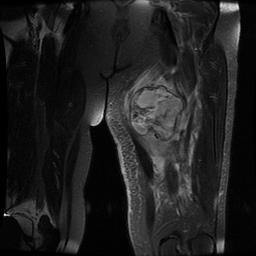

MRI